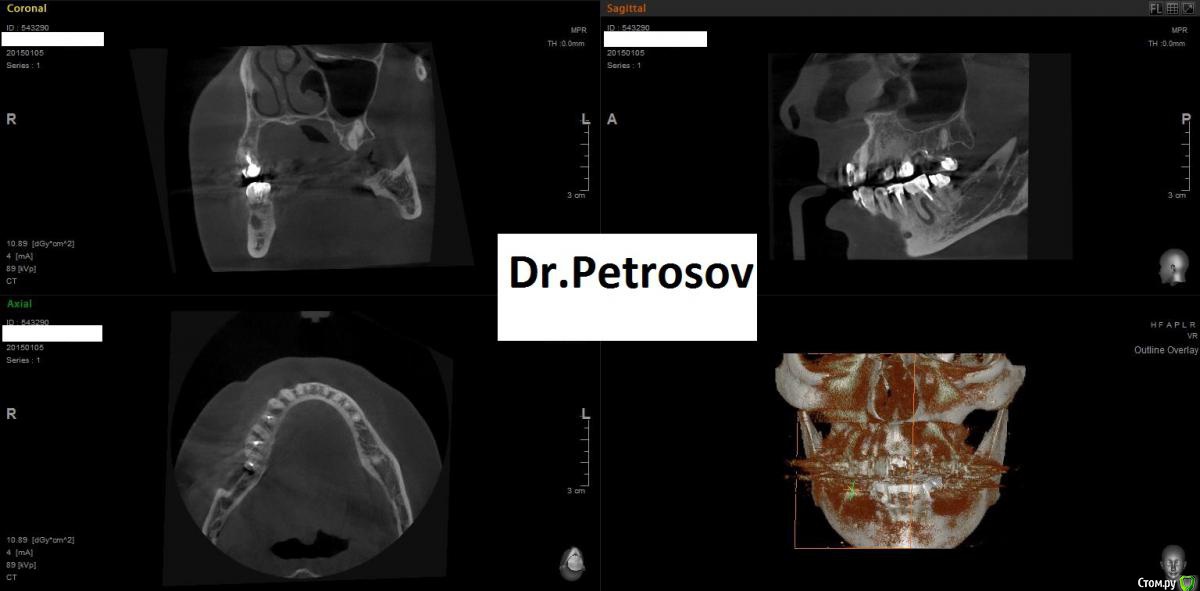

Dr.Feliks Опубликовано 11 февраля, 2015 Поделиться Опубликовано 11 февраля, 2015 Парнишка, мой сослуживец, пришел на плановый осмотр. В области зуба 3.7 увидал пародонтальный абсцесс у маргинального края десны. Со слов не беспокоит вообще, чувствует непонятный дискомфорт, но живет активной жизнью - не обращает внимание на мелочи)))Делаем КТ.На 3-м снимке результат лечения через 6 месяцев. Жду критики. Ссылка на комментарий

Dr.Feliks Опубликовано 11 февраля, 2015 Автор Поделиться Опубликовано 11 февраля, 2015 Опишите протокол инструментации/ирригации. Что чем до каких размеров на какую длину, чем и когда мыли и тд.8 ждет)Конечно хорошо бы и прицельный увидеть пол года назад. Или кт сейчас. Результат хороший.работа проведена без микроскопа и другой оптики. Коффер, Вскрытие полости зуба, расширение устьев ProtyperSx, ковер ручками до 20 на рабочую длину, затем Protyper S1,S2, ProFile 35/06, 25/06, 35/04 не доходя 1 мм до рабочей длины. Оставшийся 1 мм ручками 35 К. Ирригация: хлорка, эдта, вода, хлоргексидин + УЗ. Временное пломбирование Calasept на 2 недели. Свищ закрылся. После весь протокол ирригации и обтурация вертикалкой под СИЦ (3-й снимок с СИЦ пломбой) Ссылка на комментарий